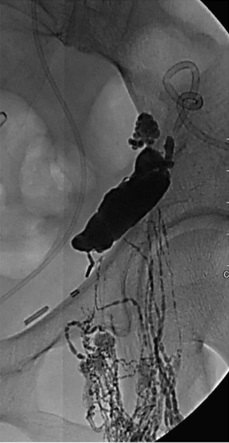

A total volume of 10 mL of lipiodol is injected using an injection pump is used at the njection rate of 0.2mL/minute. Serial fluoroscopic spot images are obtained.

Follow-up spot images of lower abdomen demonstrating upward flow of lymphatics and evidence of lymphatic leak showing in the left pelvic lymph node dissection region with pooling of Lipiodol contrast。